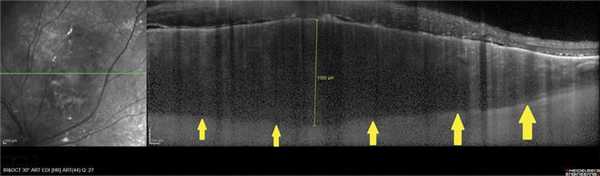

В 8 случаях выявили распространенную зону ОНЭ с дезорганизацией фоторецепторного слоя «на протяжении» от очага (рис. 6, а). В 2 случаях при анамнезе более 15 лет были выявлены зоны разрушения слоя фоторецепторов и наружных слоев сетчатки, соответствующие зонам ранее существовавшей ОНЭ (см. рис. 6, б).

Рис. 6. ОКТ-горизонтальный срез «на протяжении» от ГХ. а - пациентки Х., длительность анамнеза 3,5 года (красными стрелками указана зона ОНЭ); б - пациентки К., длительность анамнеза 15 лет (желтыми стрелками указана зона разрушения слоя фоторецепторов и наружных слоев сетчатки на месте ранее существовавшей ОНЭ, атрофия РПЭ).